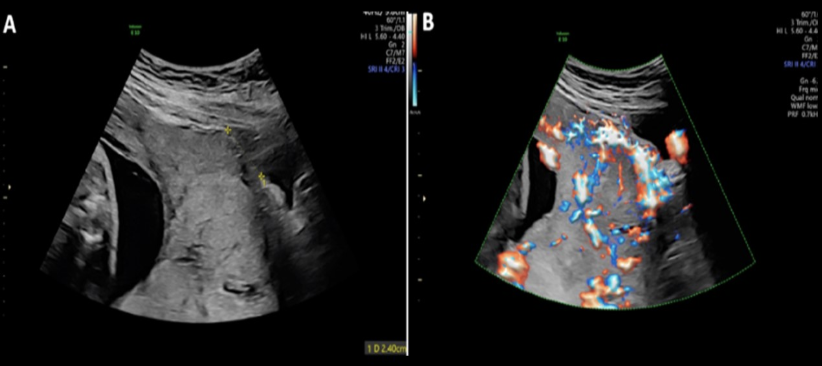

a) fetal ascites + skin edema of the abd

b) fetal ascites + pleural effusions

c) skin edema of fetal abd

d) fetal ascites